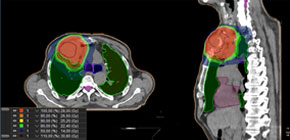

Плазмоцитома грудной стенки. Распределение дозы и результат лучевой терапии. |